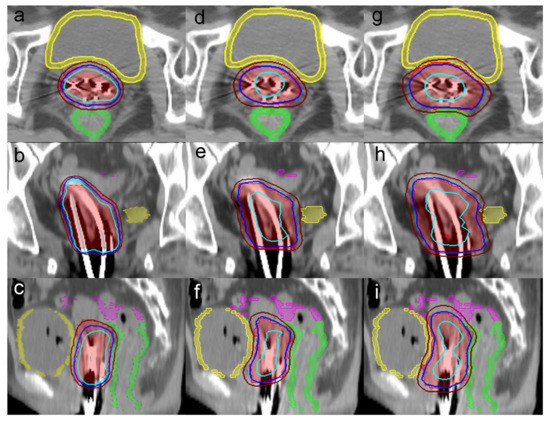

2.3. Brachytherapy Planning

2.4. CyberKnife Planning

2.5. Evaluation of the Treatment Plans